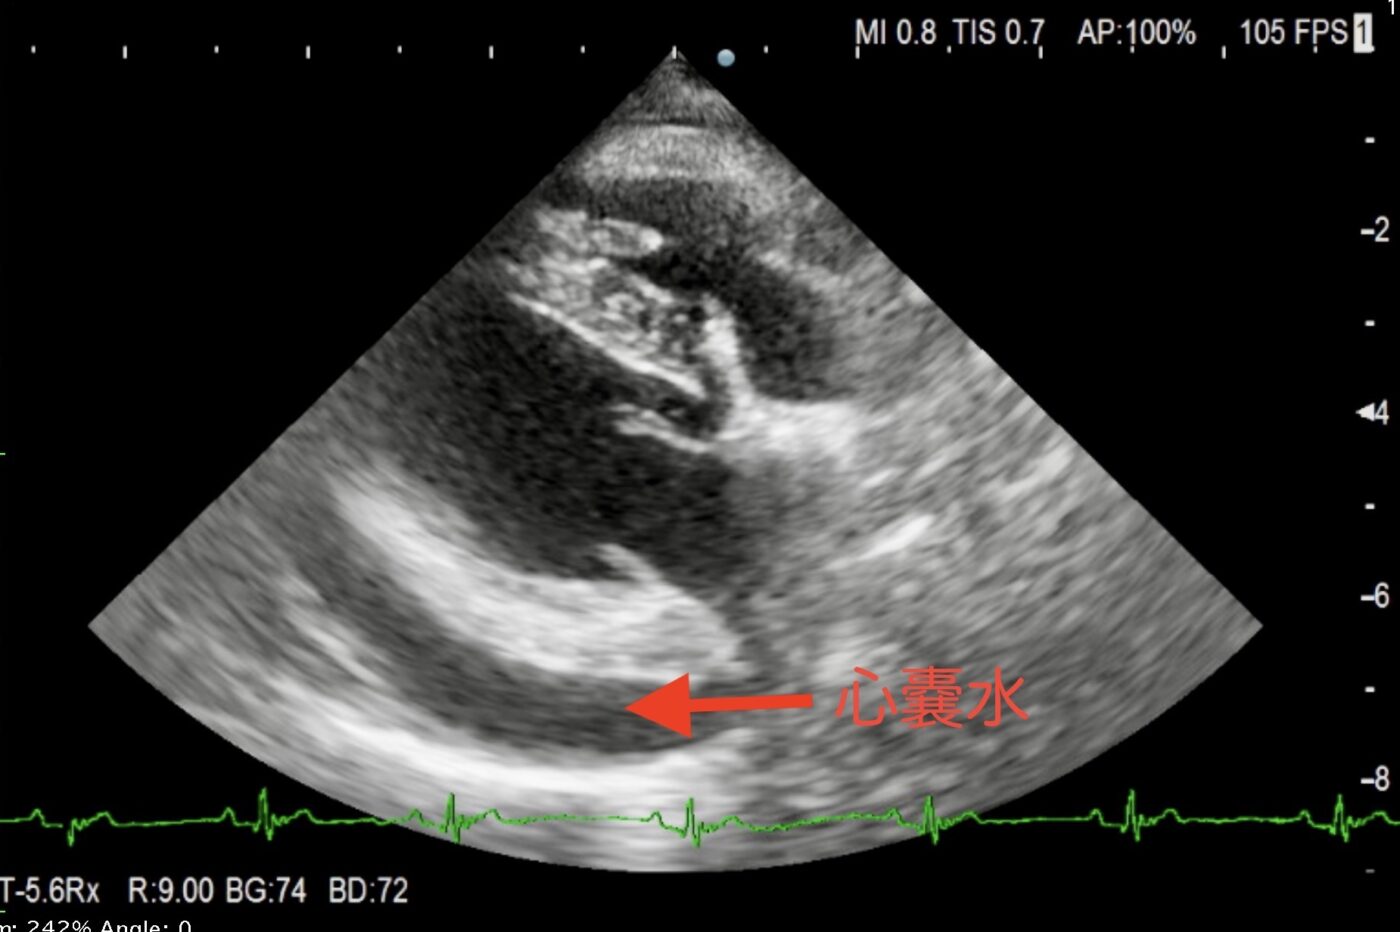

診断には心臓の超音波検査が最も適しています。

これらの原因を突き止めるのにも、心臓の超音波検査が欠かせません。